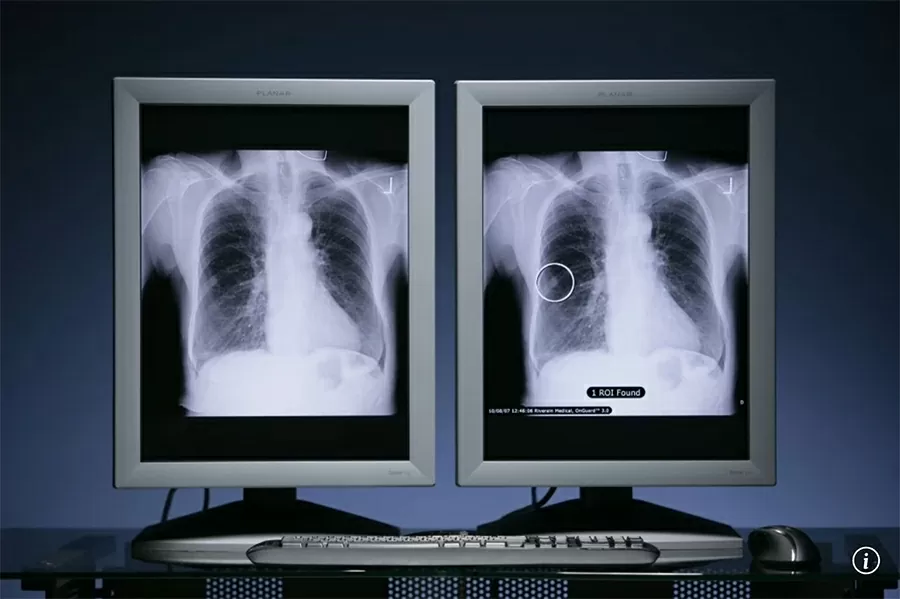

Các nhà nghiên cứu phát hiện thuốc uống zongertinib có hiệu quả vượt trội hơn phương pháp điều trị tiêu chuẩn khi điều trị ung thư phổi không phải tế bào nhỏ (NSCLC) đột biến HER2. Thuốc hoạt động bằng cách nhắm vào protein HER2 và ngăn chặn hoạt động của tyrosine kinase của protein, chịu trách nhiệm truyền tín hiệu tăng trưởng tế bào.

Loại ung thư phổi này đặc biệt khó điều trị. Không giống như các biến thể NSCLC khác, đến nay mới chỉ có một phương án điều trị được Cục Quản lý Thực phẩm và Dược phẩm Hoa Kỳ chấp thuận: liệu pháp liên hợp kháng thể-thuốc tiêm tĩnh mạch (ADC). Và các loại thuốc thuộc nhóm ADC có nguy cơ gây ra tác dụng phụ, bao gồm tiêu chảy, buồn nôn, mệt mỏi và phát ban trên da.